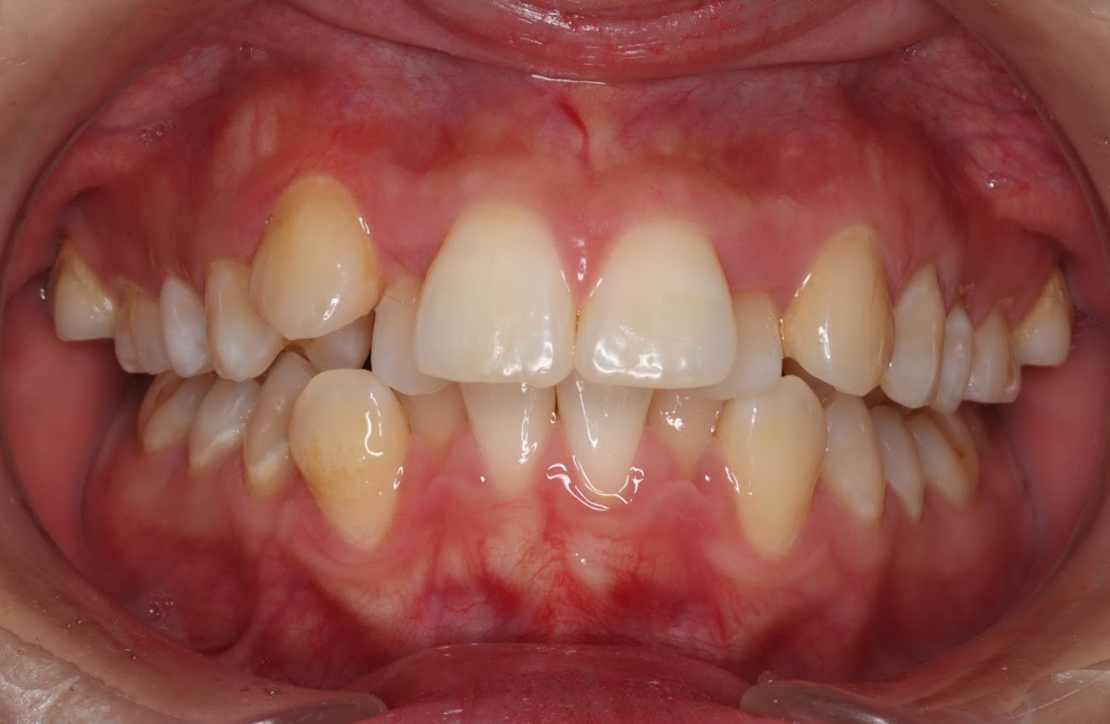

軽度のすきっ歯

上の前歯の間に隙間が空いている「軽度のすきっ歯」も、インビザラインで上だけの矯正で治療可能な歯並びです。歯と歯の間のスペースが小さい場合には、アライナーを使って歯を少しずつ寄せることで、正しい間隔に調整します。特に前歯のすきっ歯は見た目にも大きく影響するため、短期間で効果を感じやすいケースでもあります。ただし、すき間が大きすぎる場合や、噛み合わせに問題がある場合は、上下の歯を含めた矯正が推奨されることがあります。